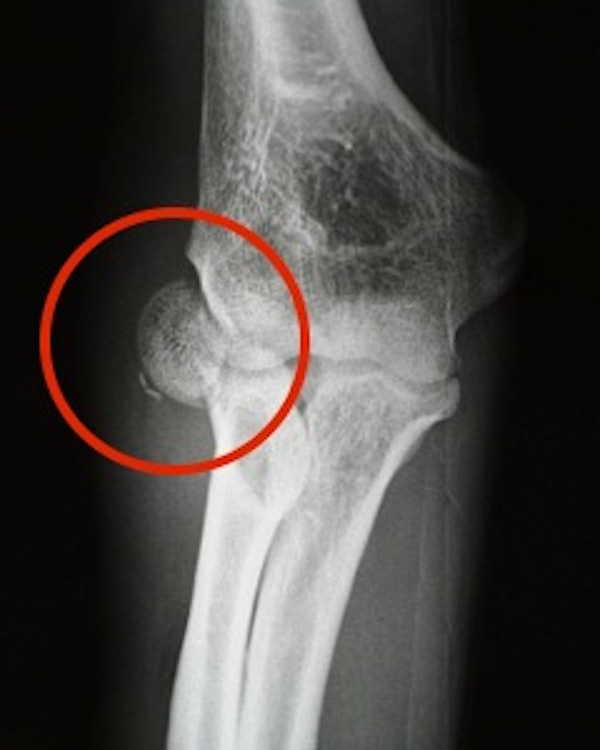

Partial articular radial head fracture, Mason type 2 according to the Chisel Fracture Radial Head   learn about the causes, symptoms, diagnosis and treatment of radial head fractures, which are common in adults and often result from a.   learn how to classify radial head fractures using the mason system, which has four types based on the degree of.  learn how to manage a radial head or neck fracture of the elbow without surgery,. Chisel Fracture Radial Head.

Oblique view of the left elbow demonstrating cortical disruption and a Chisel Fracture Radial Head  Find out what exercises to do, how long it takes to heal and when to.  learn about the causes, symptoms, diagnosis and treatment of radial head fractures, which are common in adults and often result from a.   learn how to classify radial head fractures using the mason system, which has four types based on the degree of. . Chisel Fracture Radial Head.